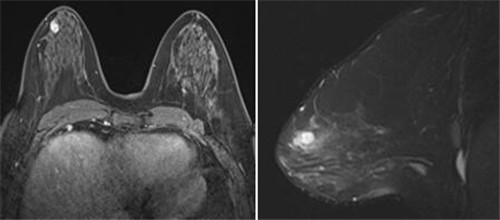

这是医院检查首例乳腺MRI,分别通过T1、T2、动态增强及TIC图对病变进行分析,诊断该病患右侧乳腺于乳头后上方病变为良性肿瘤,术后病理证实为纤维腺瘤。